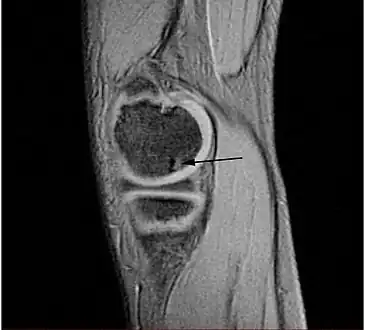

| A large flap lesion in the femur head typical of late stage Osteochondritis dissecans. In this case, the lesion was caused by avascular necrosis of the bone just under the cartilage. | |

Sagittal MRI: Linear low T1 signal at the articular surfaces of the lateral aspects of the medial condyle of the femur confirms the presence of OCD.